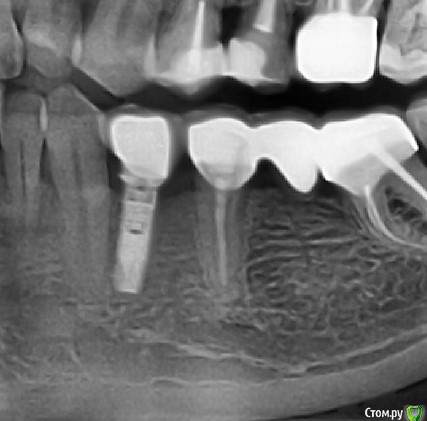

Коллеги добрый вечер. Может кто узнает систему - очень надо, со слов пациента ставил 10 лет назад. Внешне размер платформы примерно 3.5 мм, ключ подошел корейский 1.2, формирователь закрутилс(хоть и не до конца) от Osstem mini/ Внешне напоминает xive или antogyr. Буду очень благодарен.